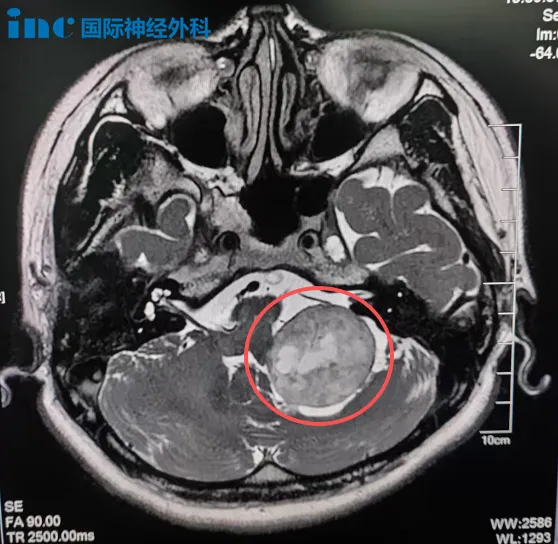

33岁的林女士意外摔倒发现左侧桥小脑角区(CPA区)藏着一个约36×32mm的占位,因手术风险过高,她选择了射波刀放疗。然而,放疗后肿瘤未明显缩小,她却开始反复出现脸部抽搐、眼周跳动,还伴有耳鸣、头晕等症状。

“虽然之前的放疗可能会增加神经与肿瘤的粘连,但我清楚这种情况该如何处理,能够在手术中尽力保护神经的完整性。”手术前,巴教授用一个形象的比喻解释手术计划:“如果把肿瘤比作一个杯子,那周围这根神经就像缠绕在杯壁上的鼠标线。手术就像要温柔、精准地解开这根线,轻轻将它从杯子上剥离下来,把神经和肿瘤分开。”最终,这台由巴教授主刀的高难度手术,在苏州大学附属第四医院顺利完成,肿瘤得到满意切除。